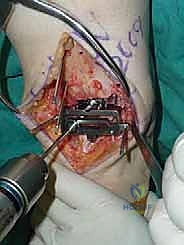

تُعد هذه الجراحة من أروع وأدق الإجراءات في عالم جراحة العظام. يقوم الأستاذ الدكتور محمد هطيف وفريقه الطبي في صنعاء بتنفيذها وفق بروتوكول عالمي صارم لضمان نسب نجاح تقارب 100٪. فيما يلي تفصيل دقيق لخطوات العملية، مدعوماً بالصور من داخل غرفة العمليات.

يقوم الدكتور هطيف بعمل شق طولي دقيق في الجزء الأمامي من الكاحل، طوله حوالي 10-15 سم. يتم تشريح الأنسجة بعناية فائقة للوصول إلى المفصل.

* الحماية العصبية الوعائية: هذه هي الخطوة الأكثر حرجاً. يتم تحديد الحزمة الوعائية العصبية (الشريان الظنبوبي الأمامي والعصب الشظوي العميق) وسحبها برفق شديد لحمايتها من أي ضرر جراحي.